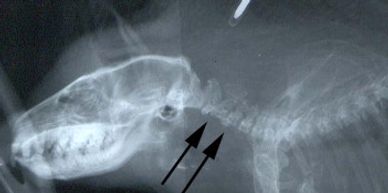

What is IVDD?

This is when spinal disks wear down, or osteoarthritis of the spine. This disease is common under humans and most animal species. As well as with hedgehogs. The only difference is, with hedgehogs it very oftens gets misdiagnosed as there are several other illnesses with similar symptoms.

Progressive hindlimb ataxia, urinary stasis, loss of proprioception, and lameness, unable to ball up.

Supportive care and corticosteroids. In some cases, the treatment only provides improvement on a temporary basis, and some other study cases shown that the disease was too advanced and was unresponsive to treatment. Some vets might prescribe additional calcium to the diet to support vertebrae that are suffering a lack of minerals.

In any situation where a hedgehog unexplained shows signs of ataxia, a proper check-up that includes radiography are crucial to identify the problem in its early stages are best.